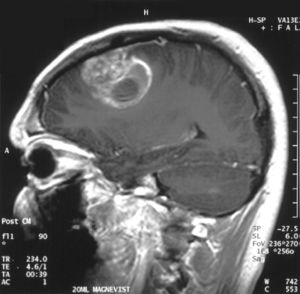

| تصوير بالرنين المغناطيسي للمنطقة التاجية يظهر الورم الأرومي الدبقي في ذكر في الخامسة عشر من عمره. | |

- اختبارات التصوير: وغالبًا ما يستخدم التصوير بالرنين المغناطيسي للمساعدة في تشخيص أورام الدماغ. في بعض الحالات، قد يتم حقن صبغة (مواد تباين) خلال وريد في ذراع المريض أثناء دراسة التصوير بالرنين المغناطيسي للمساعدة في إظهار الاختلافات في أنسجة الدماغ.

قد يساعد عدد من مكونات التصوير بالرنين المغناطيسي المتخصصة — بما في ذلك التصوير بالرنين المغناطيسي الوظيفي، وتصوير التروية بالرنين المغناطيسي وتنظير الطيف بالرنين المغناطيسي — في تقييم الطبيب للورم وخطة العلاج.

ويمكن أن تشمل الاختبارات، التصوير المقطعي المحوسب والتصوير المقطعي بالإصدار البوزيتروني.